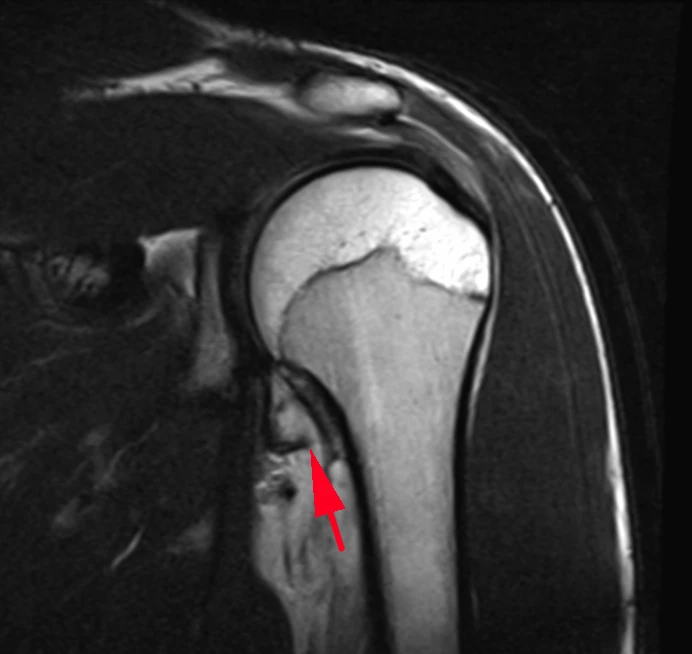

Вот такие плечики у пациента 29 лет! Во время эпидемии COVIDa-19 перенёс тяжёлую форму, лечили, в том числе, высокими дозами кортикостероидов, так что остеонекроз, который мы имеем возможность видеть в головках плечевых костей, по всей видимости, развился, как осложнение этого вида терапии. Хотя, при этой инфекции возникает ещё и гиперкоагуляция, которая и сама по себе является фактором риска развития некроза костей. В литературе такие случаи описаны и известны, есть описания развития остеонекроза даже четырёх костей одновременно (головок бедренных и плечевых костей), причём, развился он аж через полгода после окончания терапии. В нашем случае справа некроз привед к фрагментации головки плеча. Понятное дело, что функции плечевых суставов нарушены, в том числе, за счёт развития грубого вторичного артроза. Видимо, тотальная артропластика потребуется...